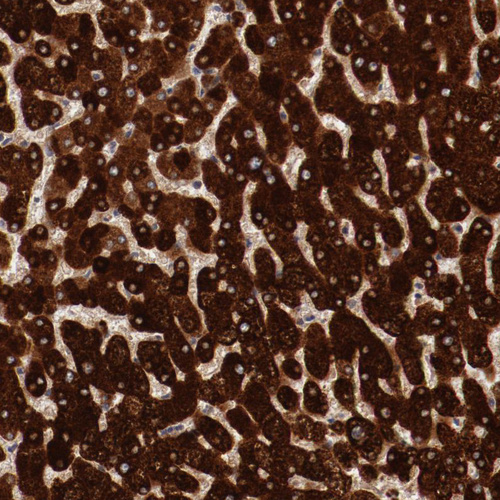

Immunohistochemistry analysis in human liver and prostate tissues using HPA002027 antibody. Corresponding MBL2 RNA-seq data are presented for the same tissues.